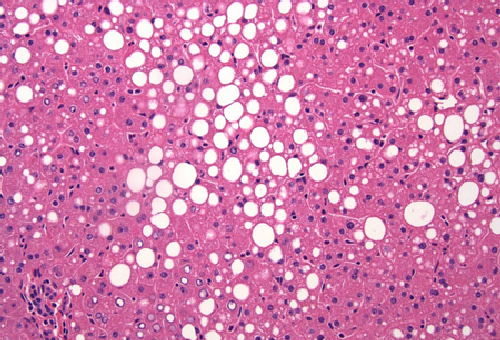

JNK promotes hepatic steatosis by suppressing the activity of the PPARa nuclear hormone receptor.